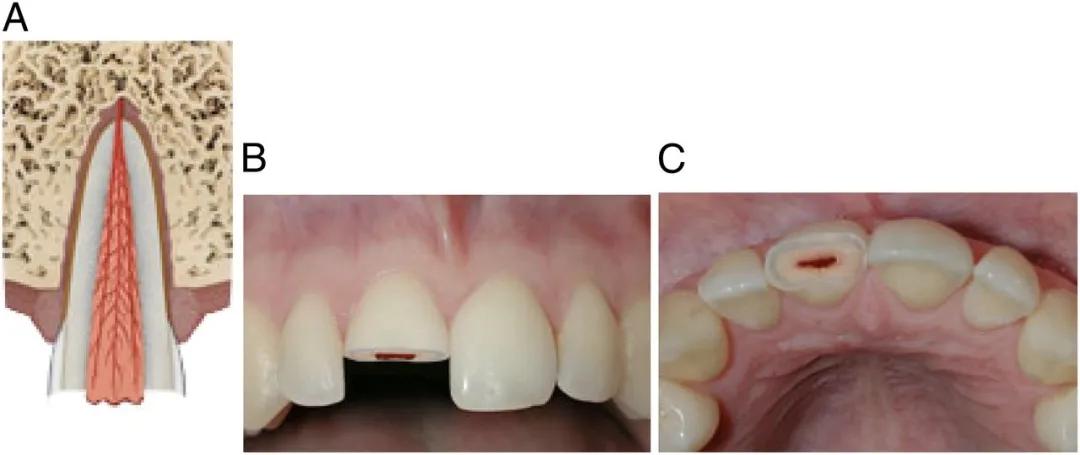

如果牙齿断得比较靠近牙根,或者摔裂了,裂缝延伸到牙根,这些情况可能会伤到牙神经,处理起来复杂一些。

图注:断牙暴露牙神经; 图源:AAP

为了防止牙神经感染,牙医通常采用一些材料,覆盖到这个露出神经的表面,然后再用材料把牙齿外形严密封闭。

如果牙齿磕断时间较长,露出的牙神经比较多,就采取牙髓切断术把受感染的这一部分牙神经去掉,把健康的牙髓保留下来,让牙根继续生长和发育。